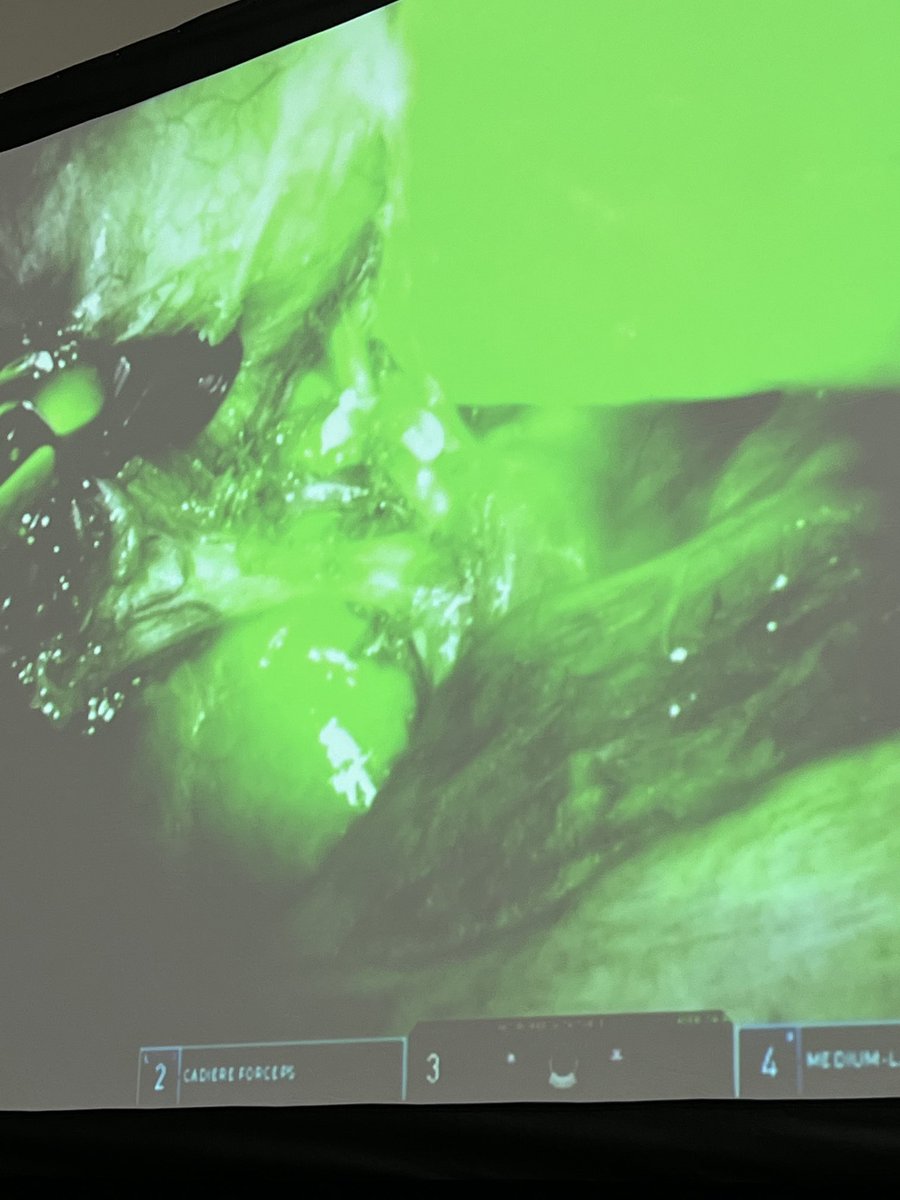

@EmorySurgery⁩ resident Jessica Labib presents on value of routine ICG in cholecystectomy, mentor ⁦@FedeSerrotMD⁩ ⁦@AnkitPatelMD⁩, ⁦@AmCollSurgeons#acscc22 GREAT JoB

Packed room and excellent presentation from our PGY4 future MIS surgeon #JessLabib #SafeChole @EmorySurgery @AmCollSurgeons @SAGES_Updates @AnkitPatelMD @EdLinEmory #ICG #IOC

FedeSerrotMD's tweet image. Packed room and excellent presentation from our PGY4 future MIS surgeon #JessLabib #SafeChole @EmorySurgery @AmCollSurgeons @SAGES_Updates @AnkitPatelMD @EdLinEmory #ICG #IOC